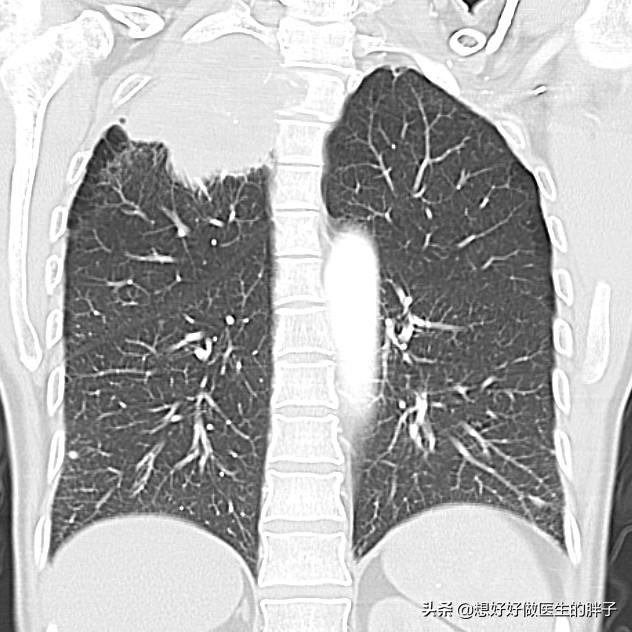

●Maladies pulmonaires.. Il est relativement rare qu'une maladie pulmonaire soit à l'origine de douleurs à l'épaule et au dos, mais il existe un type de cancer du poumon appelé "cancer de l'épaule".cancer du poumon apicalCette tumeur n'induit pas de symptômes spécifiques dans les premiers temps, mais au fur et à mesure qu'elle se développe, elle envahit lentement la plèvre et peut provoquer des douleurs à l'arrière de l'épaule.

En cas de suspicion, il est important d'effectuerTomodensitométrie des poumonsIl s'agit de préciser s'il existe un espace réservé.